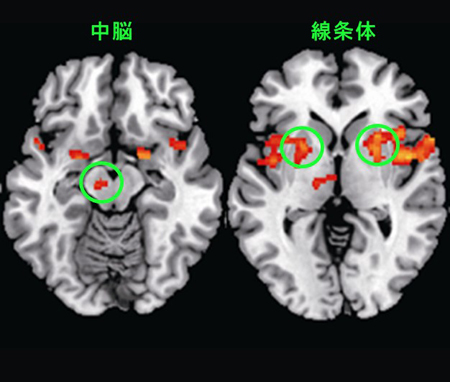

なぜ痒いところを掻くと気持ちよくなるのか? その脳内メカニズムを解明 - 生理学研究所。